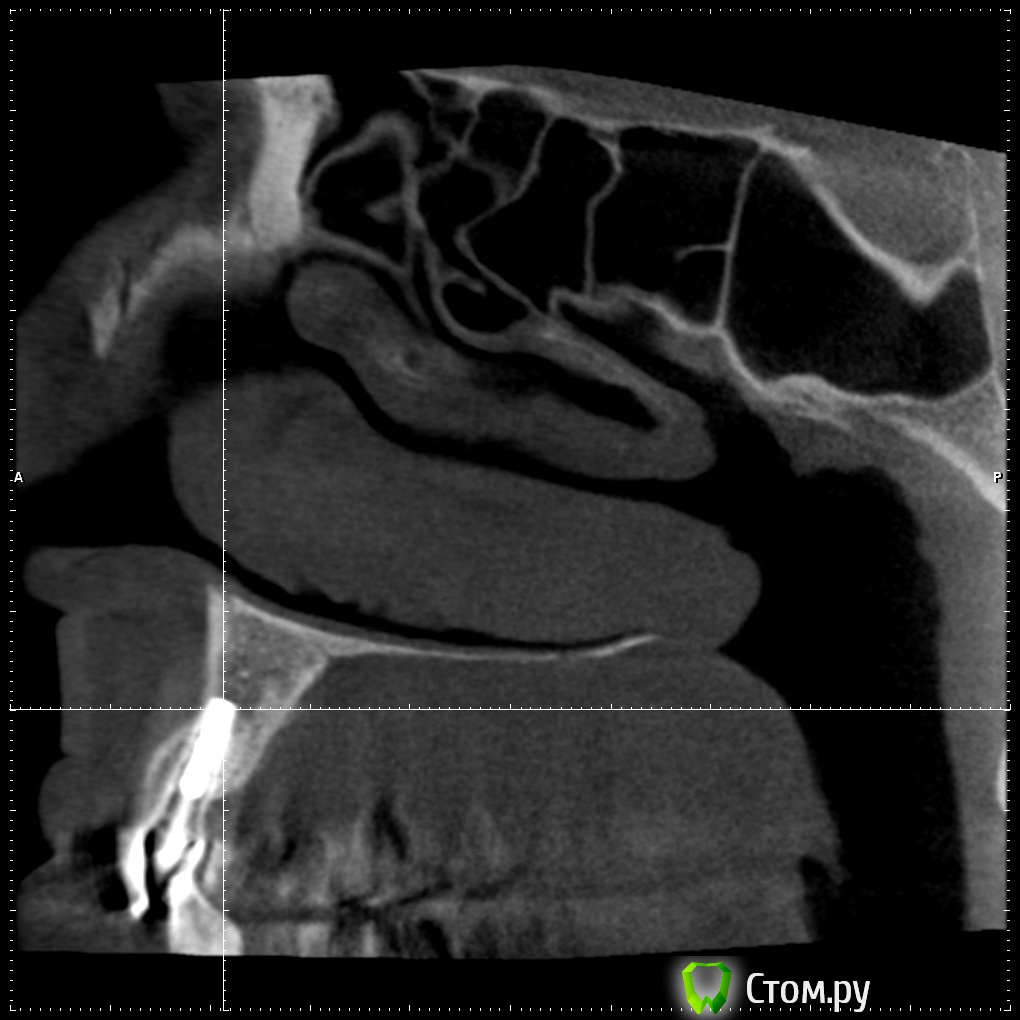

Britanez Опубликовано 2 июня, 2014 Поделиться Опубликовано 2 июня, 2014 В июле 2013 года были установлены 2 импланта 2 и 6 , 6ка с открытым синус лифтингом, в феврале 2014 установили коронки. Две недели назад обратил внимание на воспаление десны над обеими коронками,появился свищ над вторым имплатом и выделения белого цвета.Обратился к врачу, назначили пропить антибиотики 5 дней и сделать КТ. Антибиотики пропил над 6кой воспаление прошло ,над 2кой осталось,по результату КТ сказали что ушла кость и 2ку скорее всего придется удалять.Подскажите что можно сделать в данной ситуации, можно ли сохранить имплант?Ссылка на кт: http://my-files.ru/vbs51uСделал срезы кт: Ссылка на комментарий

Britanez Опубликовано 9 июня, 2014 Автор Поделиться Опубликовано 9 июня, 2014 Извините, что пишу в Вашей теме, просто хочу выразить сочувствие. Напишите потом, пожалуйста, как пойдут Ваши дела дальше, и что говорят врачи, почему произошло отторжение? А синус делали одновременно с постановкой обоих имплантов?? И ещё, выскажу просто мнение для администрации сайта и стоматологов, хотя сообщение наверняка удалят. Меня удивляет, для чего тогда сделана ветка для вопросов пациентов, когда за несколько дней ни один уважаемый стоматолог не заглянул и ничего не написал... После этого задумаешься, стоит ли размещать свои снимки, фотографии и проблемы..... Отвечу здесь если кому то интересно.Синус на 6ку делали одновременно с постановкой двух имплантов.Врачи говорят, что воспаление пошло из-за того что верхний край импланта вышел за пределы костной ткани (на втором снимке видно) и при нагрузке началось воспаление, хотя имплант стоял очень крепко ,открутить не смогли, выпиливали, чем то типа круглой коронки.Если здесь кто нибудь из врачей объяснил (подтвердил) причину воспаления, был бы очень признателен. Ссылка на комментарий

Bier Опубликовано 9 июня, 2014 Поделиться Опубликовано 9 июня, 2014 Имплантат частично стоял не в кости и кости судя по в ему было очень мало еще до имплантации. Ссылка на комментарий